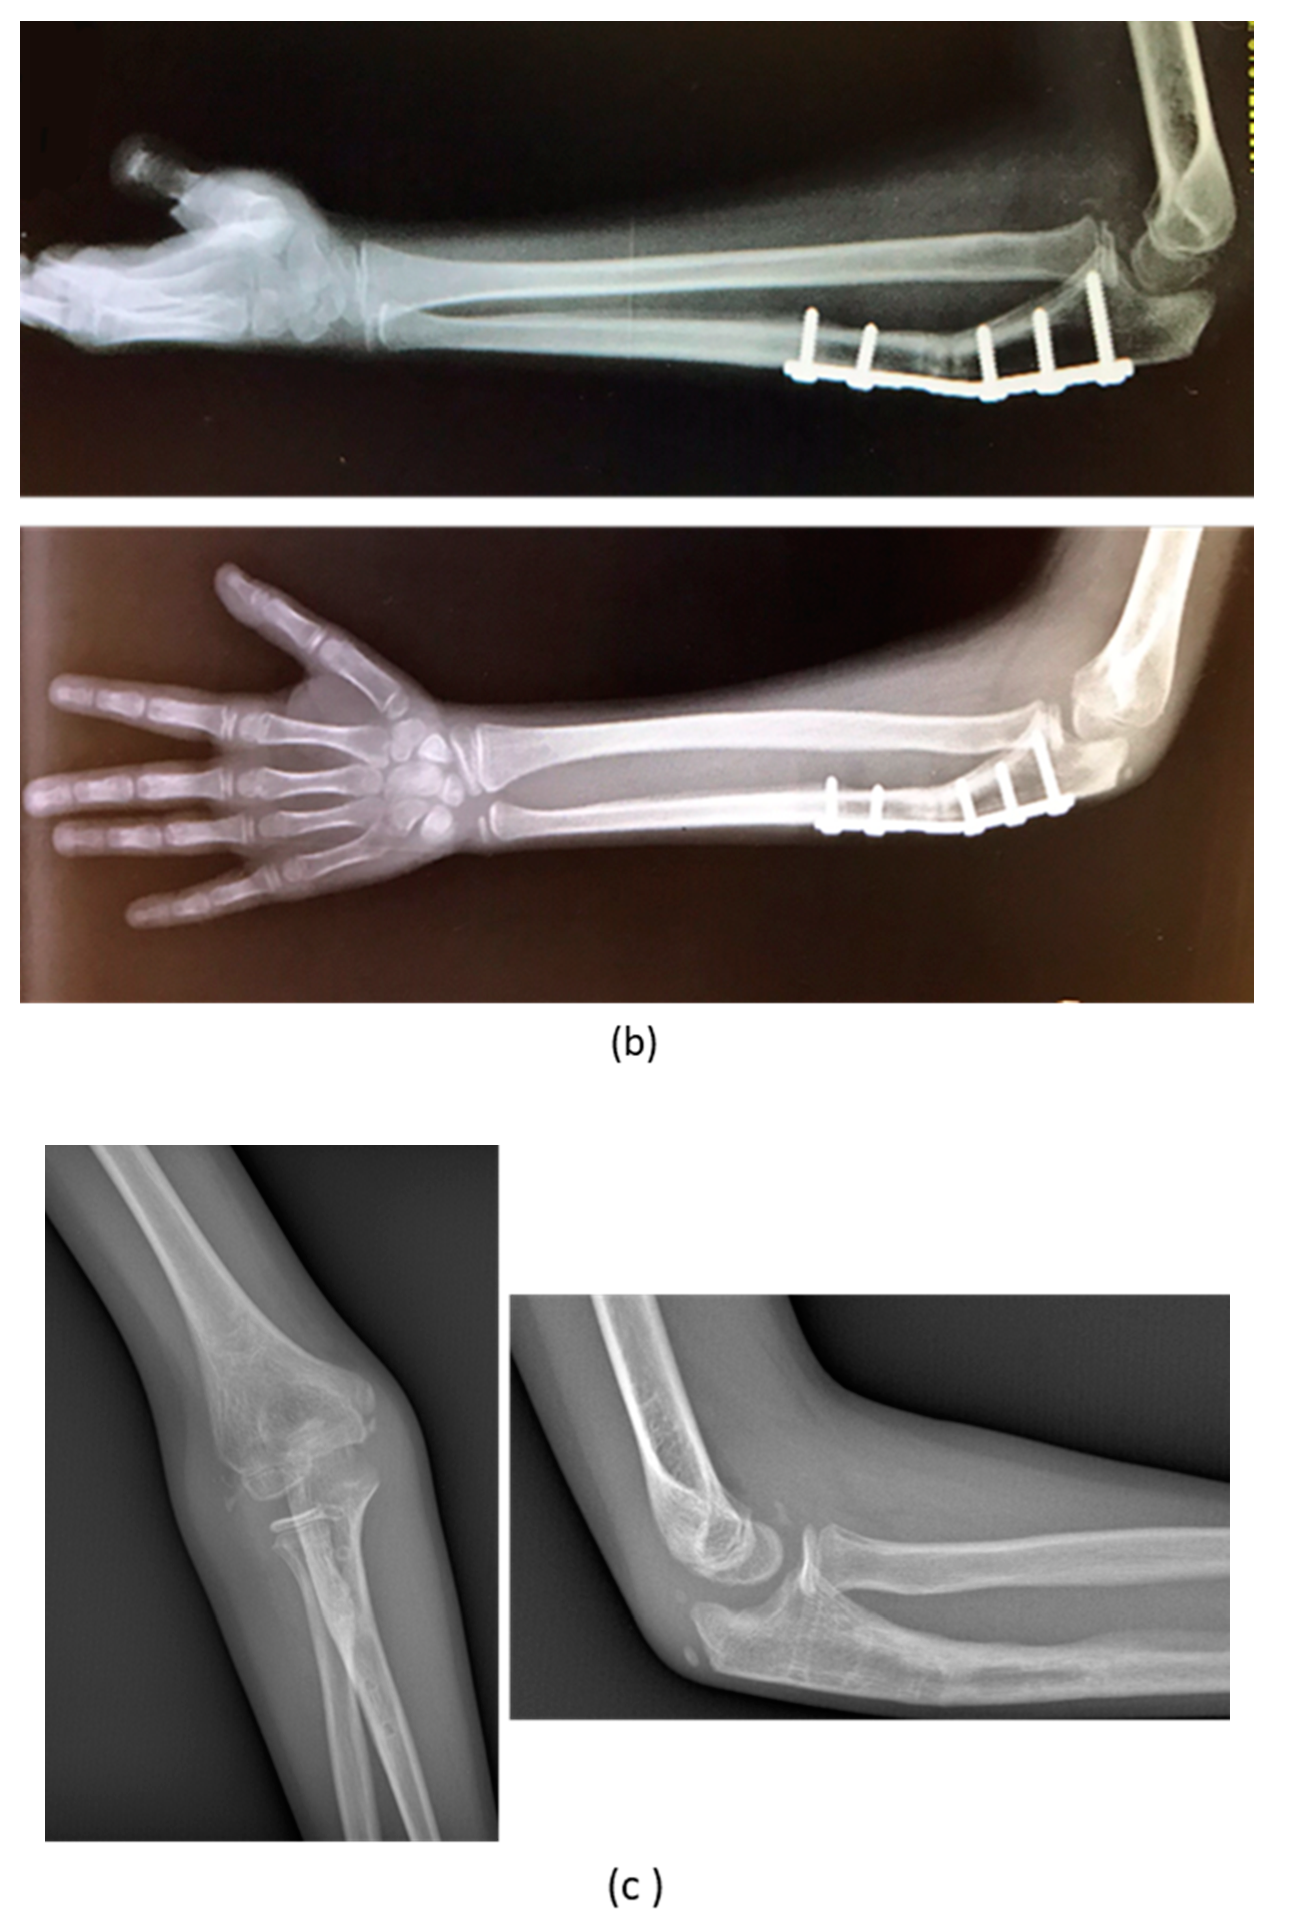

| 1 | F, 9 | Missed Monteggia Lesion | Post-traumatic | Proximal ulnar osteotomy stabilized with a 6-holes plate | None | Corrected |

| 2 | M, 13 | Focal fibrocartilagineous dysplasia | Congenital | Bifocal osteotomy stabilized with external fixator | Heterotopic bone formations | Fair (residual dislocation of the radial head with shortening of the ulna) |

| 3 | M, 15 | Post-traumatic forearm malunion deformity | Post-traumatic | Bifocal osteotomy stabilized with 1/3 tubular plate | None | Corrected |